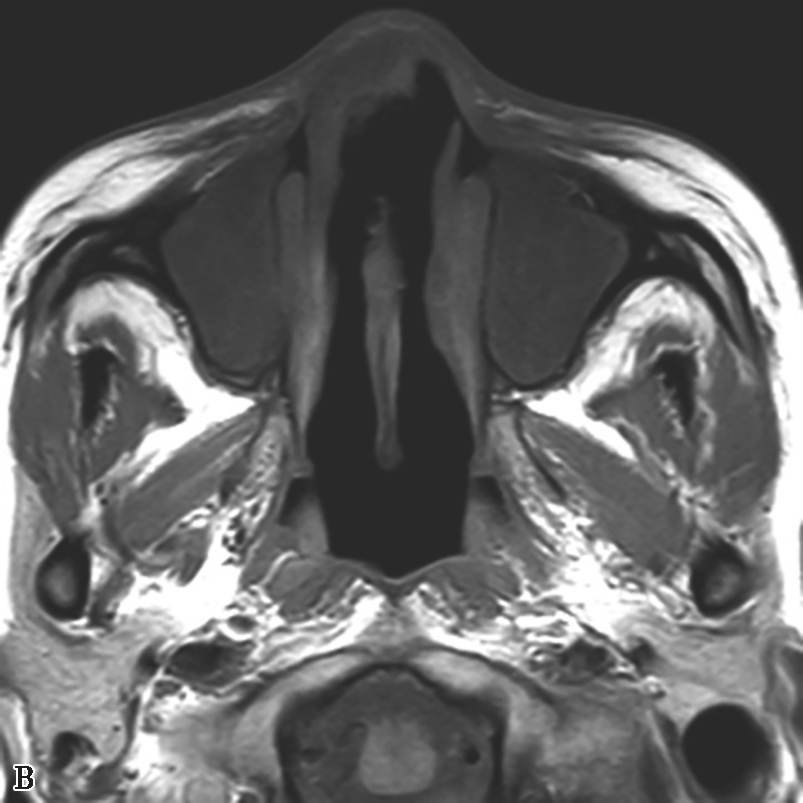

2.MRI表现

EM表现为T 1 低信号或中等信号,T 2 极低信号或信号缺失(图1-3-24C~E)。

图1-3-24 嗜酸细胞增多黏液性鼻窦炎

A、B.横断面及冠状面CT骨窗,示双侧额窦、筛窦、上颌窦及蝶窦腔充填软组织影,密度不均匀,见多发斑片状磨玻璃样密度影“双重密度影”;双侧中、总鼻道见软组织影充填;C~E.横断面T 1 WI、T 2 WI及冠状面T 1 WI,示全组鼻窦窦腔充填长T 1 、混杂短到长T 2 信号影,双侧中鼻道、总鼻道及上颌窦窦口区可见小斑片状略短T 1 混杂等到短T 2 信号影